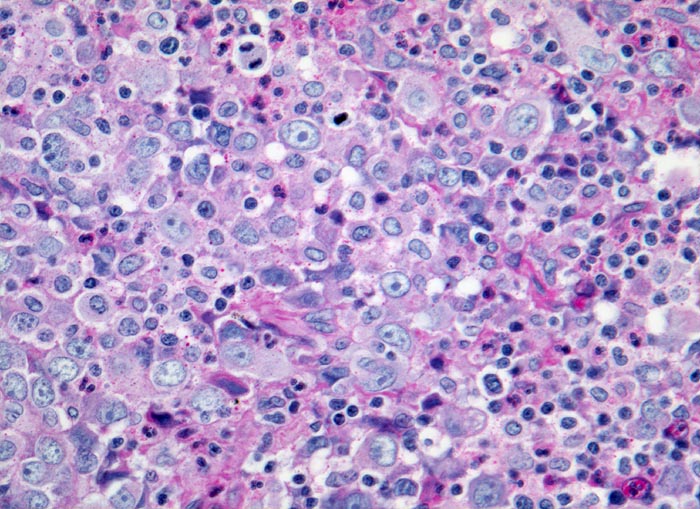

Nasopharynxkarzinom: Lymphknotenmetastase

Diskohäsives Infiltrat eines grosszelligen Tumors. Die Tumorzellen besitzen grosse helle runde oder ovale Kerne mit einem oder mehreren prominenten Nukleolen (Fehldiagnose Hodgkin Lymphom!). Zwischen den Tumorzellen Lymphozyten und Granulozyten.

Häufige Verwechslung mit Hodgkin- oder Non Hodgkin Lymphomen, da die Lymphknotenmetastasen oftmals Erstmanifestation eines sehr kleinen nasopharyngealen Karzinoms im Nasopharynxbereich sind.